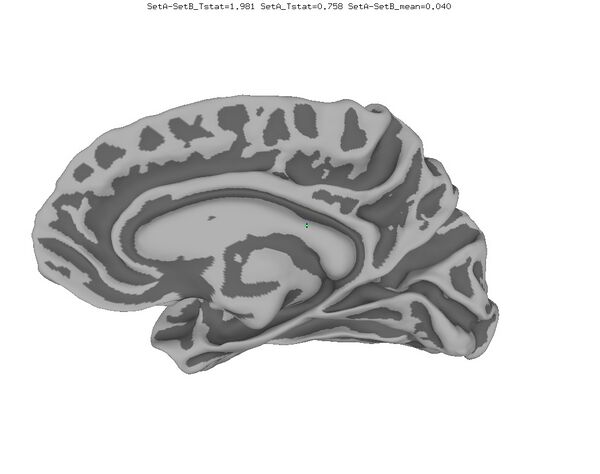

Anatomical Data

New

Old

Functional data of the Mouth vs. Eye contrast mapped to the average surface. It is hard to quantify the difference, but one way is to compare the maximum statistical values; with better intersubject alignment, these would presumably increase.

1. NEW: Max t-value for Mouth: 9.3 Eye:10.1 Eye vs Mouth: 5.6

2. OLD: Max t-value for Mouth: 7.9 Eye:8.8 Eye vs Mouth: 5.8

data from Zhu LL, Beauchamp MS. Mouth and Voice: A Relationship between Visual and Auditory Preference in the Human Superior Temporal Sulcus. Journal of Neuroscience 8 March 2017, 37 (10) 2697-2708; DOI: https://doi.org/10.1523/JNEUROSCI.2914-16.2017. Click here to download the PDF. Surface averages were not used in this paper so the bug did not affect the published results.